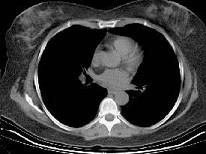

问题 女性患者,60岁,心房纤颤史5年,彩超提示房间隔占位,CT示房间隔见一椭圆形低密度影,CT值约为一300HU,边缘清楚,首先考虑为 ( )

选项 A、房间隔缺损 B、心脏转移瘤 C、淀粉样变 D、脂肪瘤 E、血栓

答案 D